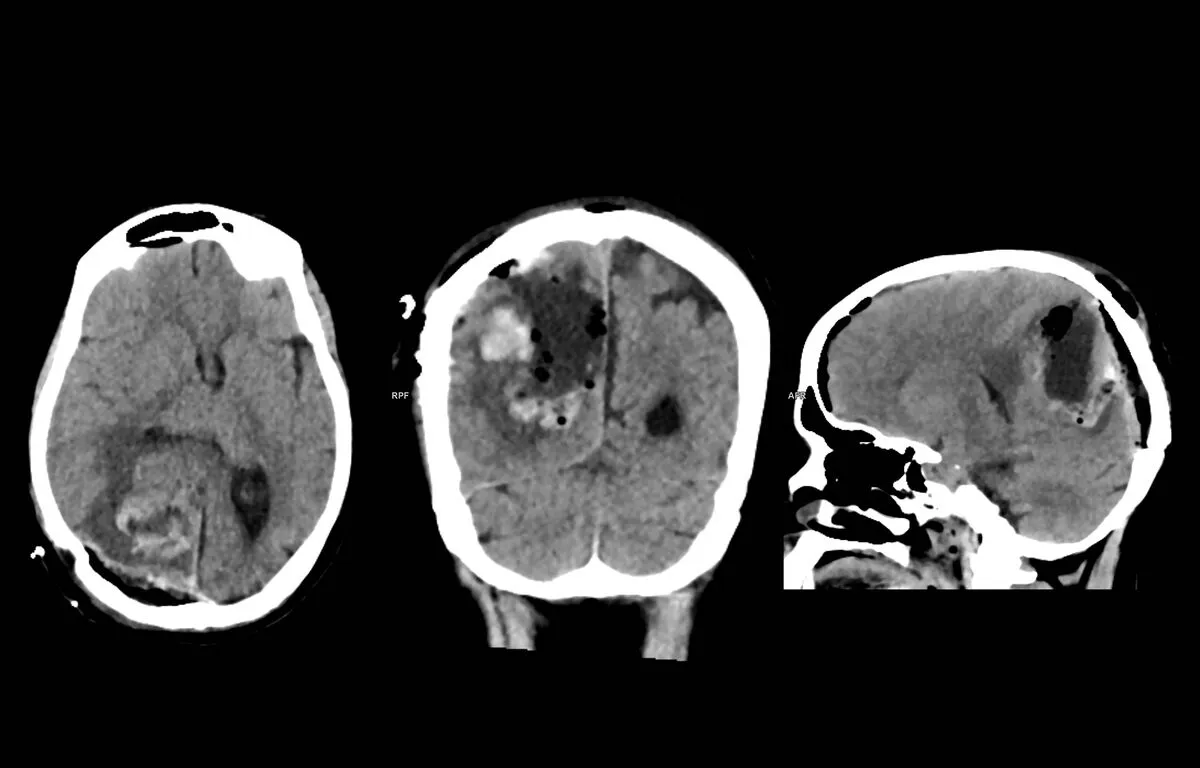

Egy természetes, az emberi agyban is jelen lévő pszichoaktív molekula, a dimetiltriptamin (DMT) biztató hatást mutatott a sztrók okozta károsodások mérséklésében. Állatkísérletekben csökkent az agyi infarktus térfogata és az ödéma, sejttenyészetekben pedig helyreálltak a sérült védelmi mechanizmusok. A kutatást a HUN-REN Szegedi Biológiai Kutatóközpont Biofizikai Intézete és a Semmelweis Egyetem Városmajori Klinikája végezte, az eredményeket a rangos szaklap, a Science Advances közölte.

A sztrók kezelésében ma is szűk az időablak és kevés a célzott lehetőség. A DMT két fronton hatott. Egyrészt védte, majd helyreállította a vér-agy gát szerkezetét és működését – ez az a biológiai „határzár”, amely normálisan kiszűri a nem kívánatos anyagokat a vérből, mielőtt az az agyba jut. Másrészt gyulladáscsökkentő mechanizmust indított: a Sigma-1 receptor közvetítésével gátolta a gyulladásos citokinek termelődését az agyban. A kezelés a sejtek működését is javította, ami kulcs az idegszövet egyensúlyához.

A tanulmány két szerzője László Marcell és Vigh Judit kimutatta, hogy a DMT-kezelés a sejttenyészetes és az állatmodell-kísérletekben helyreállította a károsodott vér-agy gát szerkezetét és érdemben csökkentette a szöveti duzzanatot, az ödémát. A szegedi társszerzők az SZBK Biológiai Barrierek Kutatócsoportjából érkeztek. Fontos megjegyezni, hogy a DMT-alapú megközelítés nem kiváltja, hanem kiegészítheti a meglévő terápiás eljárásokat – komplex, többpontú védelemmel.